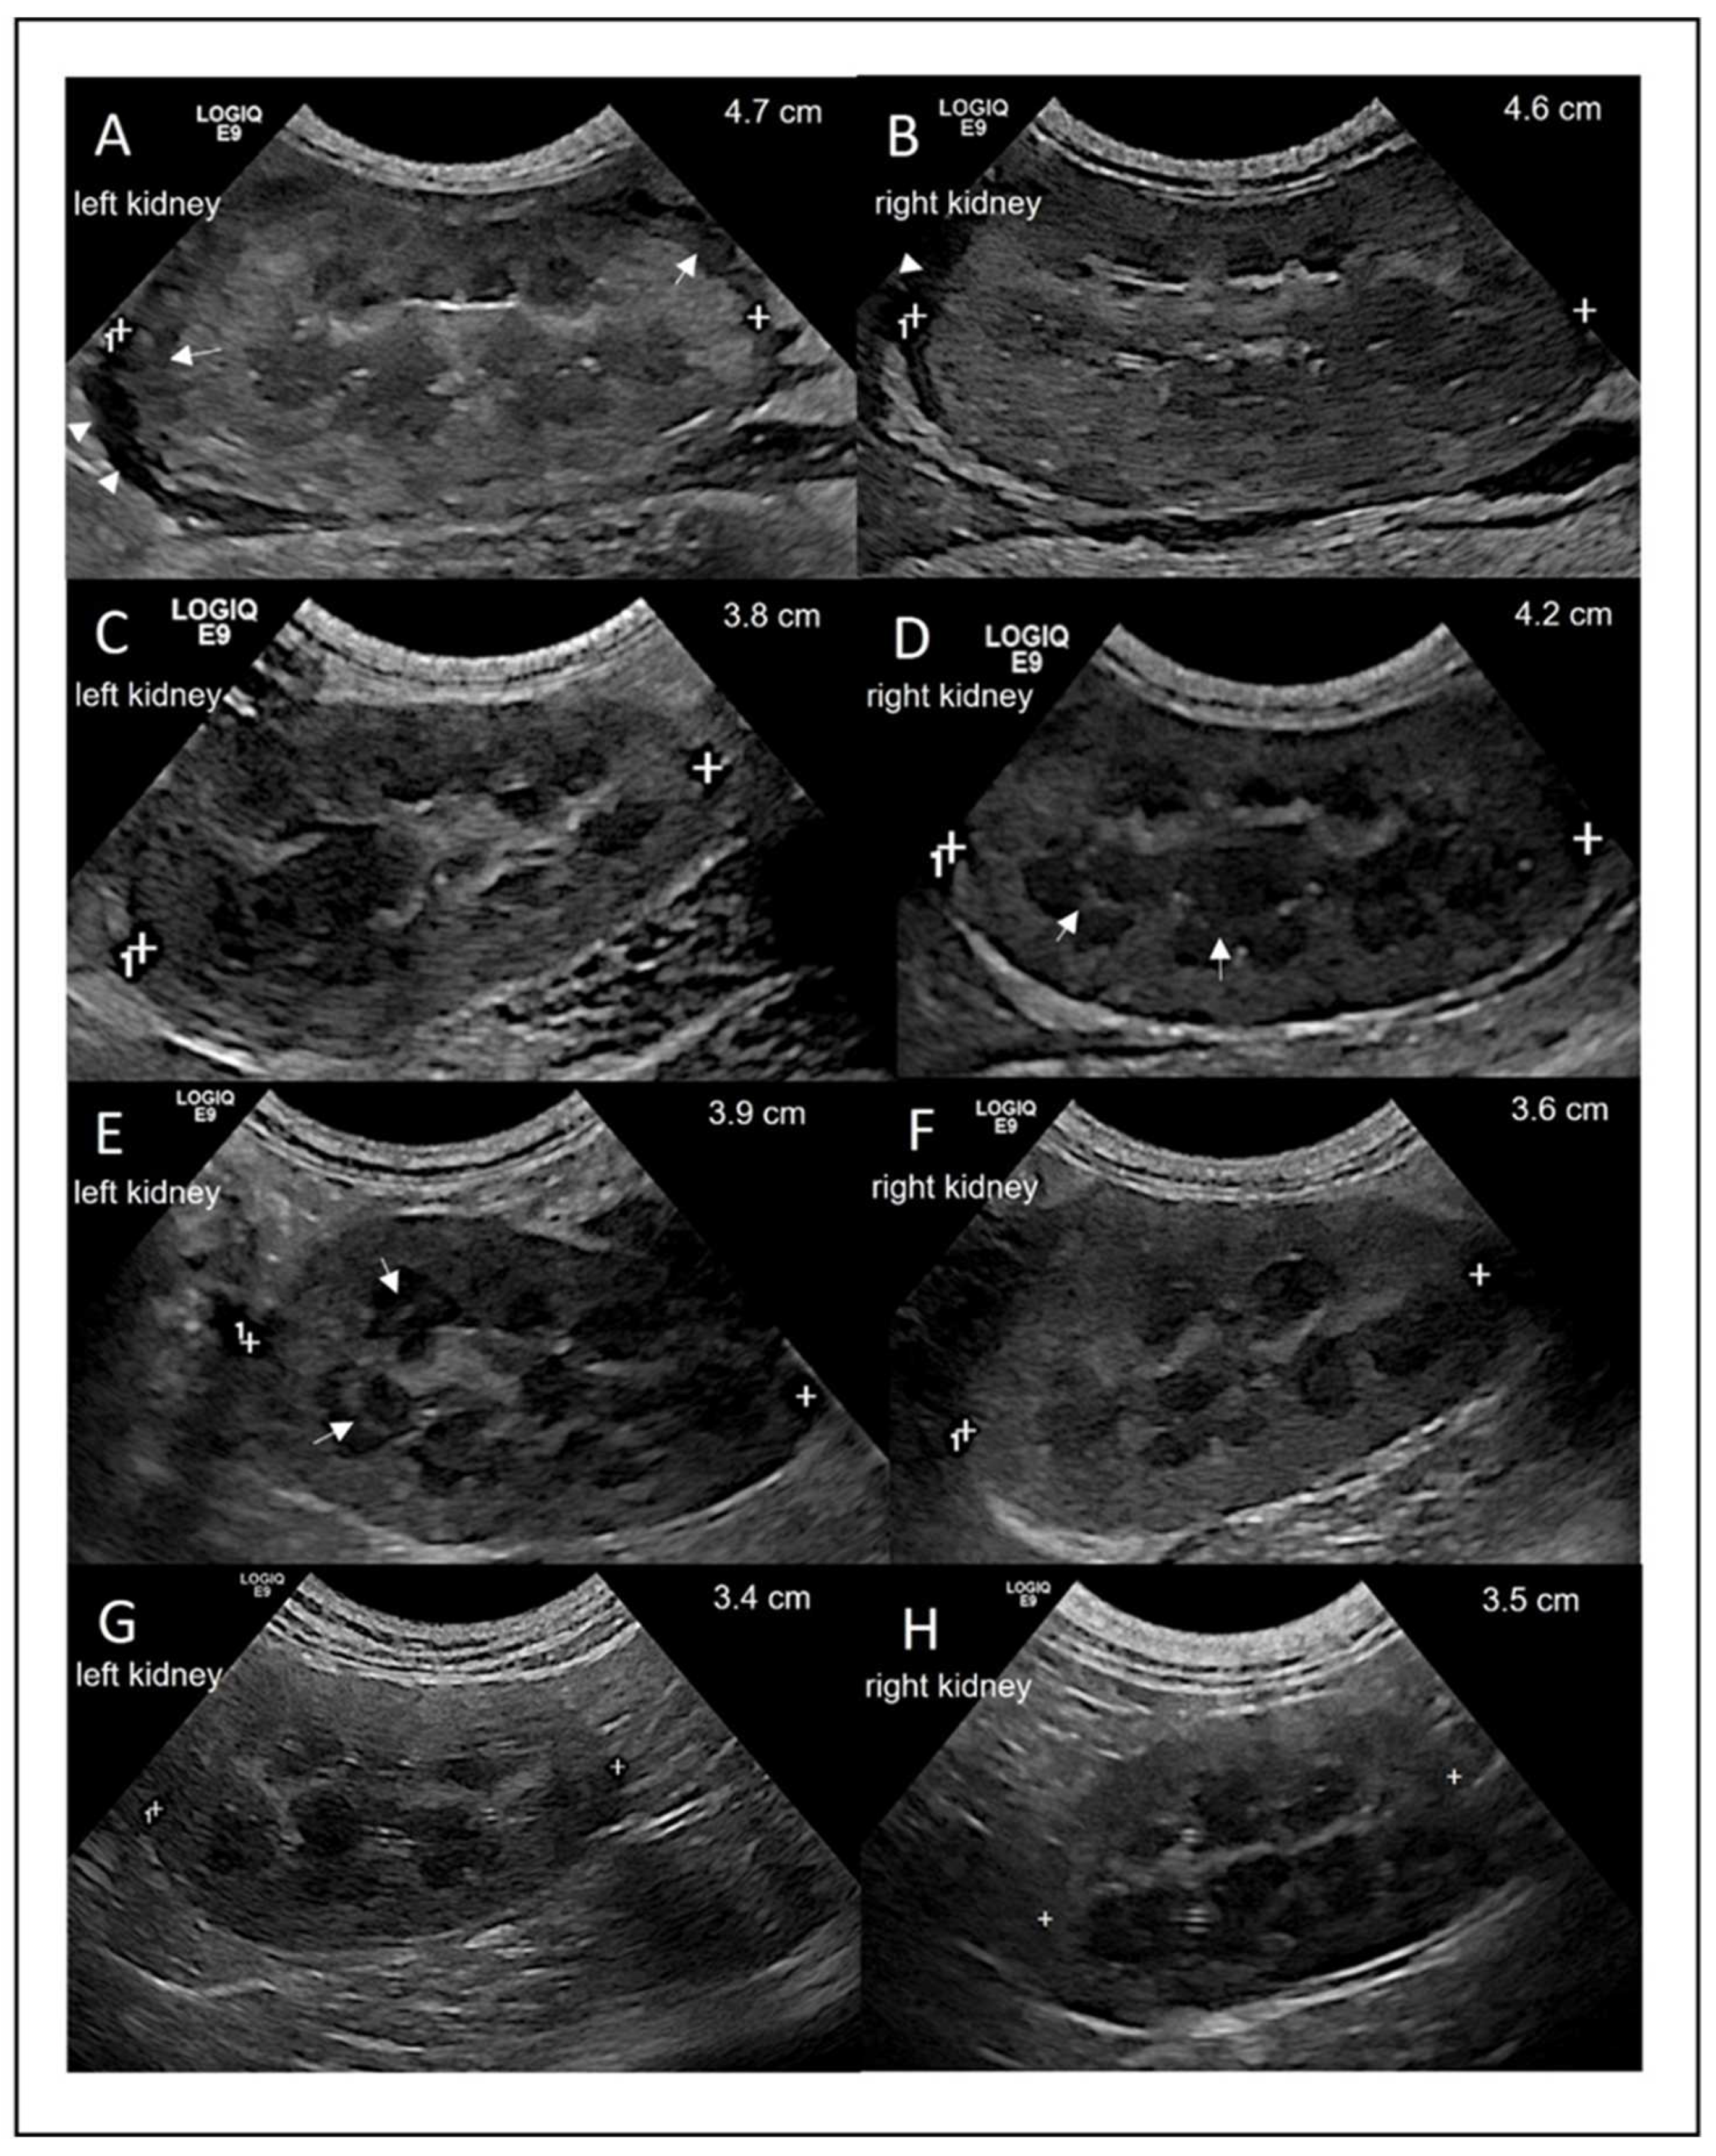

Abdominal ultrasound was performed using the Logiq E9 ultrasound machine (GE Healthcare) and an 8-MHz microconvex probe, with the cat in dorsal recumbency after clipping the fur. Upon presentation (day 0), the most notable finding was bilateral renomegaly. Regarding longitudinal measurements, the left and right kidney were 4.7 cm and 4.6 cm in size, respectively (Figure 3A,B), with a hypoechoic subcapsular rim on both sides. The surface of the left kidney was irregular, and the cortical parenchyma of both kidneys appeared hyperechoic and mottled. There was poor corticomedullary definition and a small amount of anechoic fluid in the retroperitoneal space. Intestinal lymph nodes were mildly enlarged with a homogeneous texture.

On day 7, the lengths of the left and right kidneys had decreased to 3.8 and 4.2 cm, respectively (Figure 3C,D). The cortex of both kidneys had a homogenous texture, and both kidneys had a distinct corticomedullary definition. The retroperitoneal fluid was no longer visible. A poorly defined medullary rim sign was observed in the right kidney on day 7 (Figure 3D) and in the left kidney on day 14 (Figure 3E). Both kidneys were considered normal in size, structure, texture, and echogenicity on day 56. The intestinal lymph nodes remained mildly enlarged throughout the study period.

Figure 3. Ultrasonographic longitudinal view of the left and right kidney on days 0, 7, 14, and 168. (A,B) Day 0 with arrow heads showing free fluid in the retroperitoneal area and arrows showing hypoechoic subcapsular rim. (C,D) Day 7 with arrows showing the medullary rim sign. (E,F) Day 14 with arrows showing the medullary rim sign. (G,H) Day 168 with normal size, structure, texture, and echogenicity.

The medullary rim signs, which was visible in both kidneys, also disappeared towards the end of treatment. Medullary rim signs can have various causes, but has been described in association with FIP. In a retrospective study including 243 cats showing medullary rim signs, 15 of these cats were finally diagnosed with FIP [25]. Therefore, treatment with GS-441524 likely also cured FIP-associated changes in the cat’s kidneys.